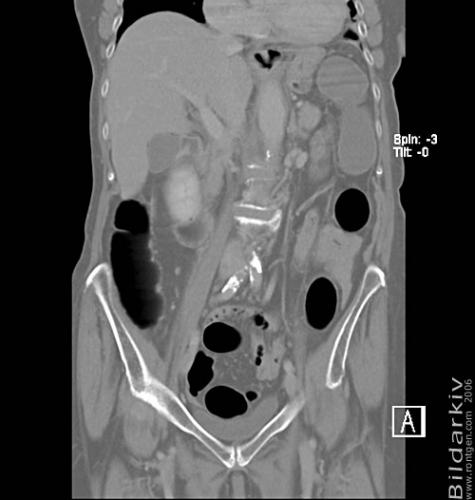

CT colon 26

Datortomografi av tjocktarmen (colon) med infunderad luft i tarmen samt med kontrast i blodbanan. Koronar bildserie.

CT multislice 16